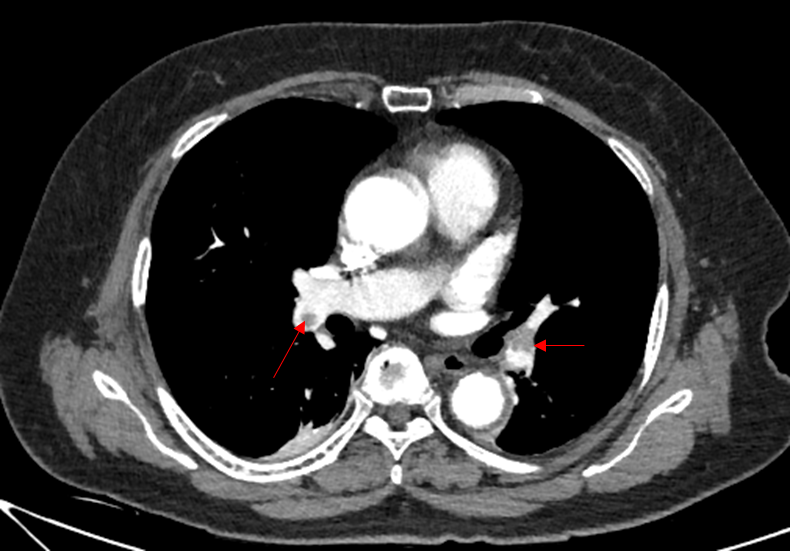

Img | CXR: 정상 CT: Thrombus at pulmonary a. |

급성 호흡곤란, 정형외과적 수술력, D-dimer elevation, CT 소견으로 보아 PTE로 진단한다.

• 이에 촬영한 CT상 실제로 pulmonary a.에 thrombus가 관찰되므로, PTE로 진단한다.

• 대동맥박리(aortic dissection): 본 증례의 흉부 CT상 aorta 내부에 false lumen 등의 구조물이 관찰되지 않는다.